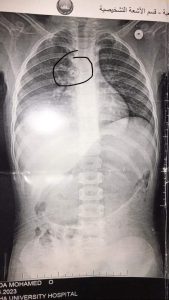

تمكن فريق طبي بقسم جراحة القلب والصدر بمستشفى بنها الجامعي من إنقاذ طفلة تبلغ من العمر سنتين ونصف ابتلعت خرزة شخشيخة أطفال واستقرت في القصبة الهوائية وجرى استخراجها، حيث كانت تلعب بشخشيخة أطفال ففتحتها وبلعت إحدى الخرز عن طريق الخطأ فنزل للقصبة الهوائية وأدى لانسداد مجرى التنفس.